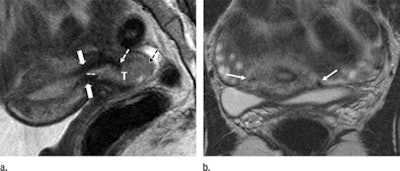

Two radiologists interpreted the results and rated tumor presence on a scale of 1, meaning there was no evidence of a tumor, to 5, meaning a tumor was definitively present. The pair also measured tumor size, the distance between the tumor and internal os, and the presence of cancer in the cervix.

Each reader identified nine patients with a tumor-to-internal-os distance of 5 mm or less at MRI, with seven (77%) of nine patients identified by both radiologists. For each reader, radical hysterectomy was required for nine of nine patients (100%) with a distance of 5 mm or less between the tumor and internal os.

"Our results suggest that tumor distance of 5 mm or less from the internal os at MRI is a statistically significant adverse imaging feature that identifies patients who are likely to require radical hysterectomy," the authors concluded. "Furthermore, MR imaging after a conization with negative margins is useful for confirmation of the absence of tumor in the remaining cervix."